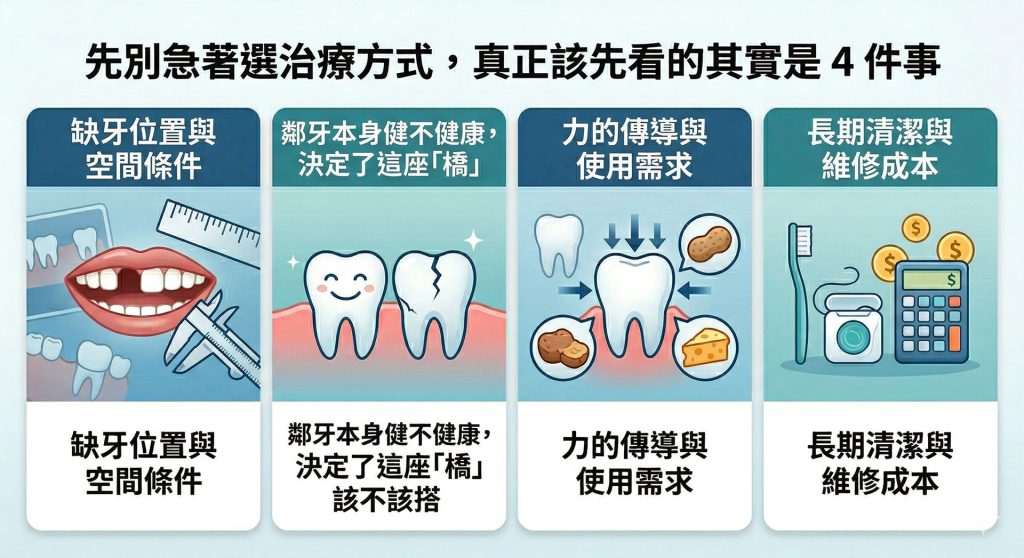

先別急著選治療方式,真正該先看的其實是 4 件事

1. 缺牙位置與空間條件

2. 鄰牙本身健不健康,決定了這座「橋」該不該搭

3. 力的傳導與使用需求

4. 長期清潔與維修成本